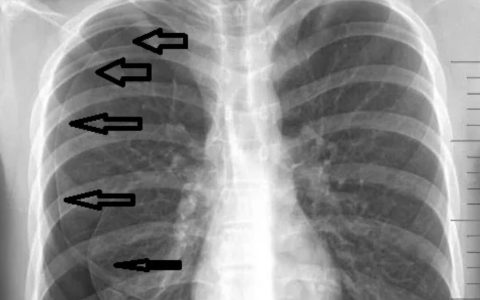

图像显示脊髓脊膜膨出,是一种神经管缺损,脑膜和脊髓通过椎管的缺损疝出。如果在妊娠早期给予母亲叶酸,可降低发生神经管缺陷(隐性脊柱裂、脊膜膨出或脑膜脊髓膨出)的风险。在成人中,叶酸缺乏引起无神经系统症状的巨幼红细胞性贫血。叶酸缺乏见于酗酒者、孕妇、溶血性贫血患者和服用甲氨蝶呤等抑制叶酸代谢药物的患者。叶酸存在于未煮熟的蔬菜和水果中。维生素 B12 缺乏也会引起巨幼细胞性贫血,但也会产生神经系统症状。这些症状包括远端神经病变和由于脊髓后柱和外侧柱以及周围神经脱髓鞘导致的位置觉丧失。

正确答案:C